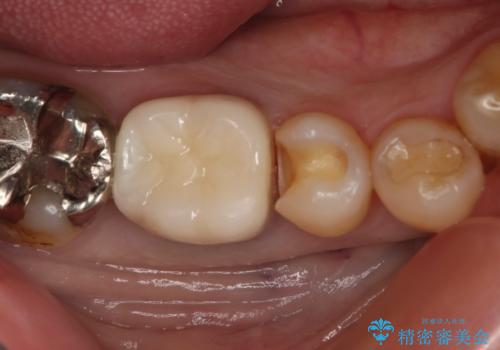

- 保険で治療された右下5番をセラミックにやり変え希望の患者様です。

切削量などを考慮し、セラミックインレーでの治療を選択しました。

古い材料と虫歯を全て除去した上で形成・印象を行い、セラミックインレーを装着しています。